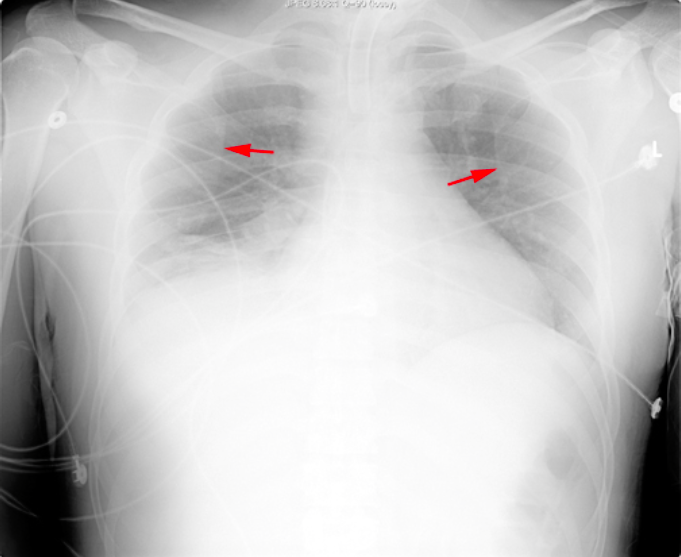

What view is this?

AP View